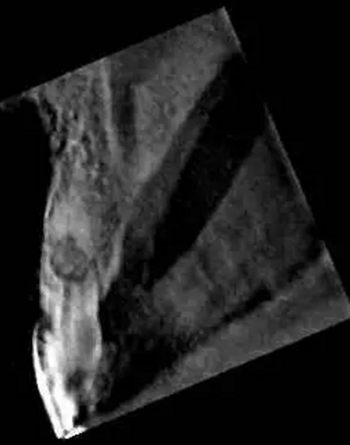

左上中切牙近遠(yuǎn)中有牙色充填體,邊緣繼發(fā)齲,牙齒不松動(dòng),輕微叩痛,患牙冷測(cè)遲鈍,牙齦未見異常。X線片示:充填體周圍繼發(fā)齲壞近髓,根中部大面積低密度影,蟲噬狀,內(nèi)部結(jié)構(gòu)顯示不清晰,根尖周未見異常。錐形束CT(CBCT)顯示根中部?jī)?nèi)吸收多處可疑穿孔,缺損內(nèi)可見菜花狀鈣化物影像

近期研究和病例報(bào)告均顯示CBCT有助于牙根吸收病例的診斷[3, 6, 13]。本病例中使用CBCT判斷缺損大小、內(nèi)容物形狀和根管壁可能側(cè)穿孔的位置,起到了輔助診斷治療的作用。